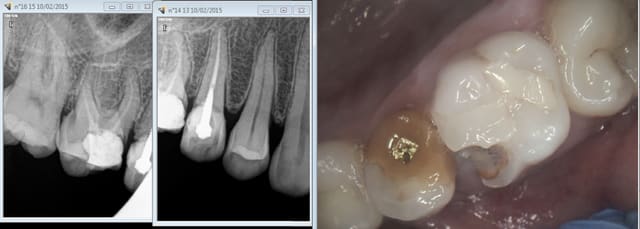

chicot29

A la radio les patients pigent que dalle ( et meme certains praticiens apparemment vu l'endo de qualité une fois de plus sur la 16 ) . Une photo bien zoomée les éclairent.

Capture d e cran 2015 02 10 09.52 - Eugenol